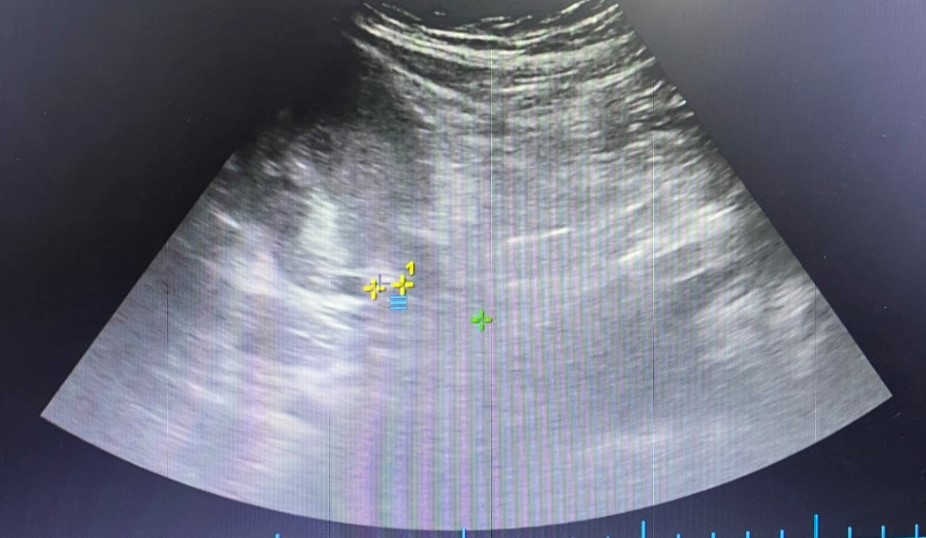

Bệnh nhân M.N, 31 tuổi ở quận Hải An, Hải Phòng vào Bệnh viện đa khoa Quốc tế Hải Phòng trong tình trạng đau mạn sườn phải, đau tăng dần lan xuống hạ vị ở tuần thai 31. Qua thăm khám và các chỉ định cận lâm sàng cần thiết, bác sĩ phát hiện người bệnh có sỏi niệu quản 1/3 trên, viêm thận bể thận phải, thận giãn độ 2, các chỉ số viêm nhiễm tăng cao. Bệnh nhân được điều trị nội khoa nhưng tình trạng đau nhiều không đỡ, sốt, tiểu buốt, rắt. Sỏi niệu quản khá to, kết hợp tuần thai lớn gây chèn ép niệu quản, điều trị nội khoa không hiệu quả cùng các biến chứng nguy hiểm như nhiễm trùng, giãn thận, viêm thận… có thể gây nguy hiểm cho cả mẹ và thai nhi. Trước tình trạng thai phụ như vậy các bác sĩ Khoa Ngoại thận tiết niệu – Nam học đã rất cân nhắc và hội chẩn để đưa ra quyết định nội soi tán sỏi niệu quản cho bệnh nhân. Kết quả tán sỏi thành công, bệnh nhân và thai nhi đều an toàn.

Ở trường hợp khác, bệnh nhân L.C, 28 tuổi vào Khoa cấp cứu, Bệnh viện đa khoa Quốc tế Hải Phòng trong tình trạng cơn đau quặn thận trái ở tuần thai 26. Bác sĩ cũng phát hiện bệnh nhân có sỏi niệu quản trái sát thành bàng quang, sỏi thận nhỏ 2 bên, thận giãn độ 1, hội chứng nhiễm trùng. Các phương pháp điều trị nội khoa không hiệu quả, bệnh nhân được thực hiện nội soi tán sỏi niệu quản. Trong suốt quá trình thực hiện, kíp thực hiện đã vô cùng thận trọng để đảm bảo an toàn cho cả thai phụ và thai nhi. Ca phẫu thuật được thực hiện rất thành công, viên sỏi đã được tán hết. Sau mổ, người bệnh đã hết đau, sức khỏe thai nhi hoàn toàn ổn định.

Theo TS.BSNT Phạm Việt Hà – Giám đốc chuyên môn hệ Ngoại, Bệnh viện đa khoa Quốc tế Hải Phòng chia sẻ: Thai phụ có kèm sỏi tiết niệu sẽ rất khó trong cả chẩn đoán và phẫu thuật bởi phụ nữ mang thai chỉ có thể áp dụng siêu âm mà không chụp Xquang hay CT. Cạnh đó, khi phẫu thuật, thai chèn ép gây khó khăn cho việc đưa ống soi lên niệu quản và vào bể thận; khó khăn trong việc sử dụng thuốc nhất là thuốc tê, thuốc gây mê vì có nguy cơ ảnh hưởng đến thai nhi. Tuy nhiên, phẫu thuật nội soi tán sỏi được ghi nhận là phương pháp ít xâm lấn, không có vết mổ và rất an toàn, bệnh nhân hồi phục nhanh chóng, đảm bảo an toàn cho sản phụ và thai nhi. Thai phụ khi có sỏi đường tiết niệu cần đến cơ sở y tế có đầy đủ trang thiết bị và đội ngũ y tế chuyên sâu về sản khoa và phẫu thuật tiết niệu để được thăm khám, phát hiện bệnh, điều trị kịp thời và hiệu quả.